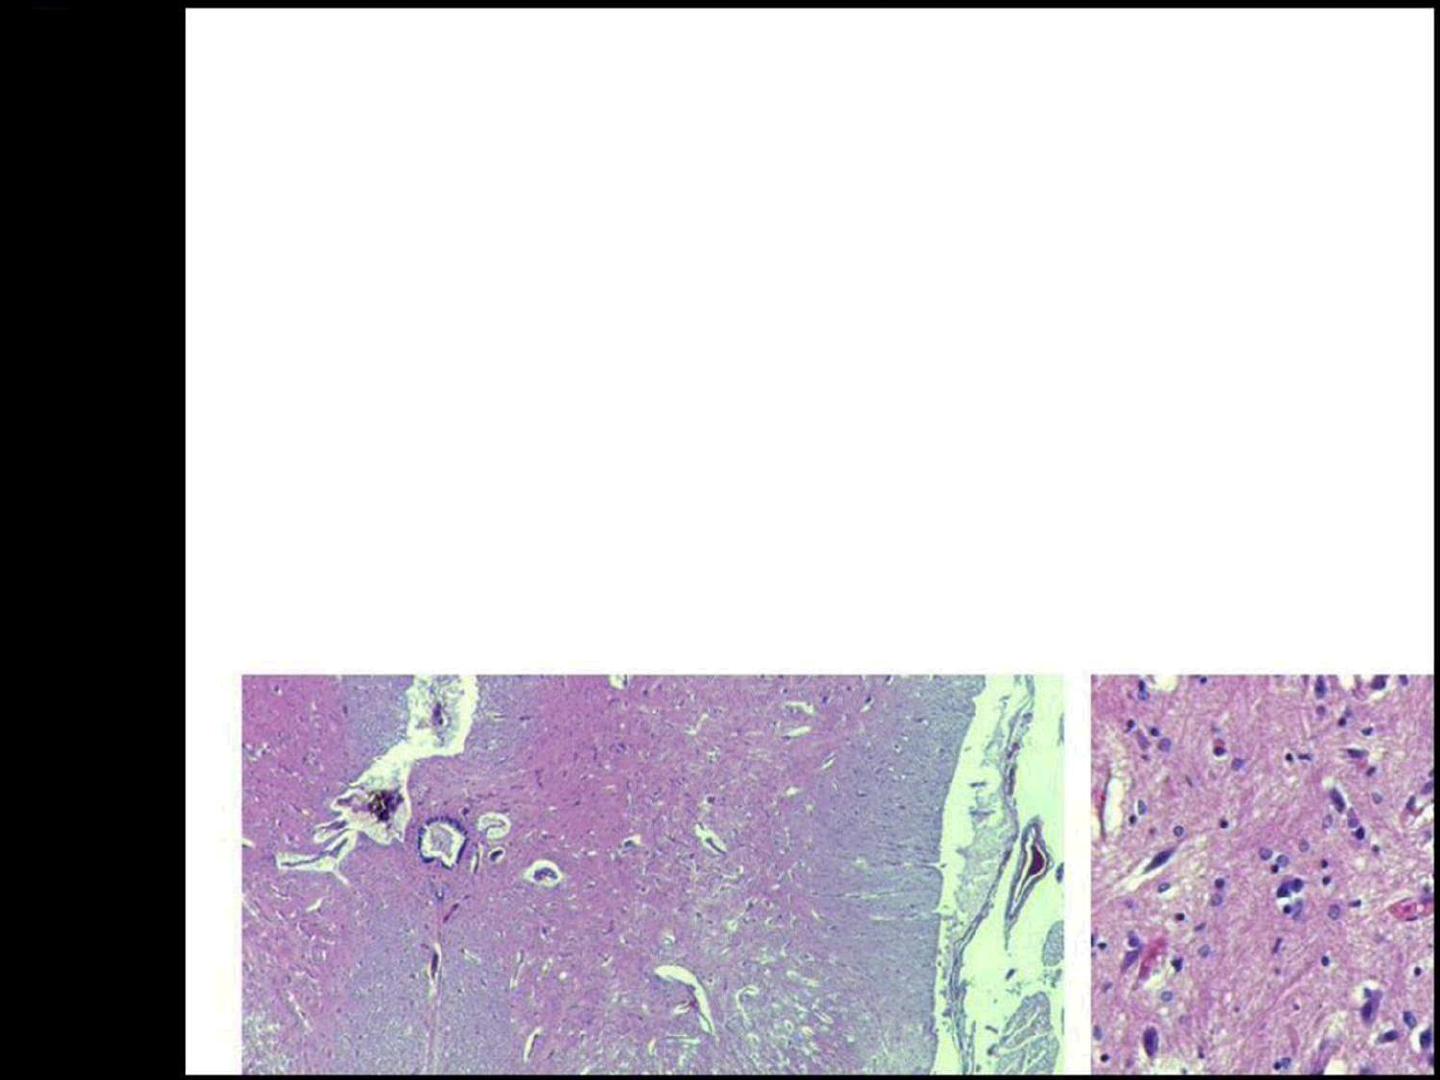

SG

SB

La moelle épinière a, en coupe transversale, une forme ovoïde.

Sa face antérieure est marquée par un sillon profond : le sillon

ventral médian.

Sa face postérieure montre un sillon plus étroit : le sillon dorsal

médian.

De part et d'autre de ces sillons, se détachent :

-en avant, les racines antérieures (motrices);

-en arrière, les racines postérieures (sensitives).

Ces racines convergent pour donner naissance à un nerf rachidien.